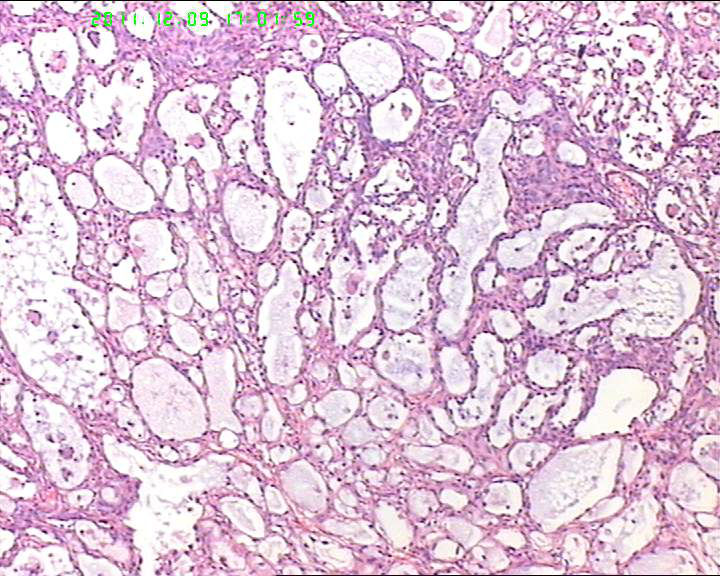

各位老师,会诊一下,49岁卵巢肿物,到底是什么呢?

盆腔包块4个月,13*8*7cm 大小,囊实性,实性区菜花状、灰白质脆,局部半透明。

有腺腔样结构,内衬靴钉样细胞,还可见透明细胞,首先考虑透明细胞癌,鉴别诊断:内胚窦瘤。内胚窦瘤的网状结构内衬是扁平的上皮。

有鞋钉样细胞,首先考虑透明细胞癌。要除外卵黄囊瘤,浆乳癌。